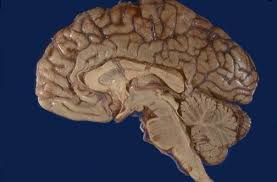

Neuroanatomy Tutorials From The Internet Pathology Laboratory For Medical Education Webpath Hosted By The Unive Human Body Systems Brain Facts Brain Issues